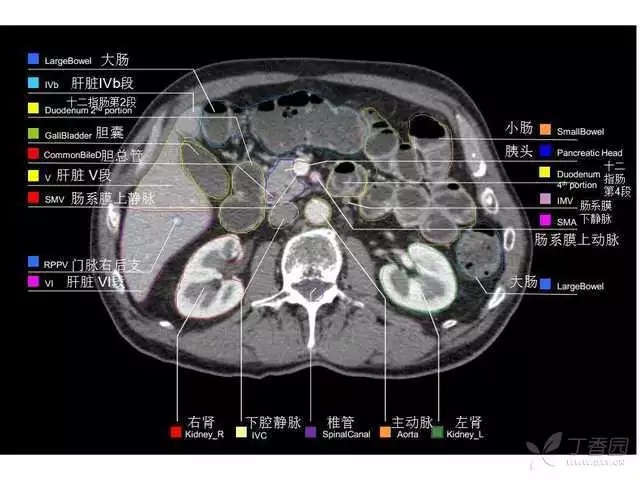

腹部肝脏高清CT断层的图谱

全腹部高清CT图谱,淋巴结彩色图谱,血管解剖图谱大汇总!

超声肝脏分叶及分段

肝脏分段和基本解剖学标志